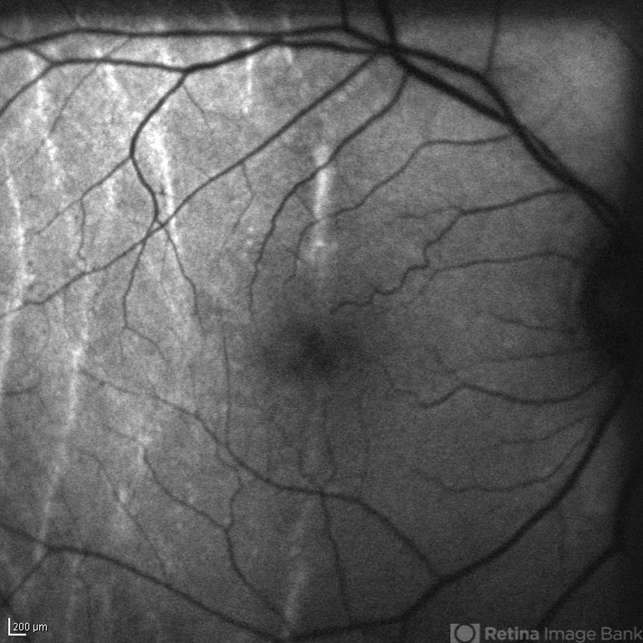

- Autofluorescence image of a 75-year-old patient with hypotony, 2 weeks after trauma, 2 years after extracapsular cataract surgery.